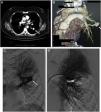

Thoracic CT scan and angiogram images of the pulmonary arteriovenous malformation. (A) The axial thoracic CT image (mediastinal window) shows an aneurysmal sac (arrow), with a connection to a sub-segmental branch of the upper branch of the pulmonary artery. (B) 3D-volume rendering CT image that shows an aneurysmal sac with a connection to a sub-segmental branch of the upper branch of the pulmonary artery, and at the lower end to a pulmonary vein (*). (C) Selective left pulmonary artery branch angiogram showing the pulmonary arteriovenous malformation (arrow). (D) Postembolization pulmonary arteriogram with complete occlusion of the pulmonary arteriovenous malformation.

In December 2016, after an upper digestive endoscopy, a respiratory infection was diagnosed. In order to control the response to therapeutics, she underwent a chest radiography revealing a pulmonary nodule. The CT-scan showed a nodule, 20mm in diameter, located in the apical segment of the left lower lobe (Fig. 1). Upon contrast injection, on the arterial phase, a complete fill-in of this nodule was seen, which formed an aneurysmal sac, with a connection to a sub-segmental branch of the upper branch of the pulmonary artery, and to a pulmonary vein, at the lower end. No internal thrombosis was observed. The diagnosis of PAVM was made. The patient was asymptomatic and denied episodes of hemoptysis, trauma, thoracic surgery, and no personal nor family history of epistaxis. At examination, no telangiectasia was seen in the oral cavity, lips, face or fingertips. The pulmonary auscultation was normal, with no audible thoracic murmur. Peripheral oxygen saturation was normal, with 97% at resting and in room air. Human chorionic gonadotropin (hCG) and hCG beta chain were low (<1UI/L and <0.04ng/mL respectively). The echocardiography and spirometry were normal.

Based on the history of molar pregnancy, and on the imaging demonstrating a typical PAVM in a territory where a metastasis of trophoblastic tumor had regressed with treatment, we diagnosed isolated PAVM developed on pulmonary sequelae of a metastatic molar pregnancy. The patient underwent percutaneous coil vaso-occlusion, with no complication and a good immediate angiographic result.